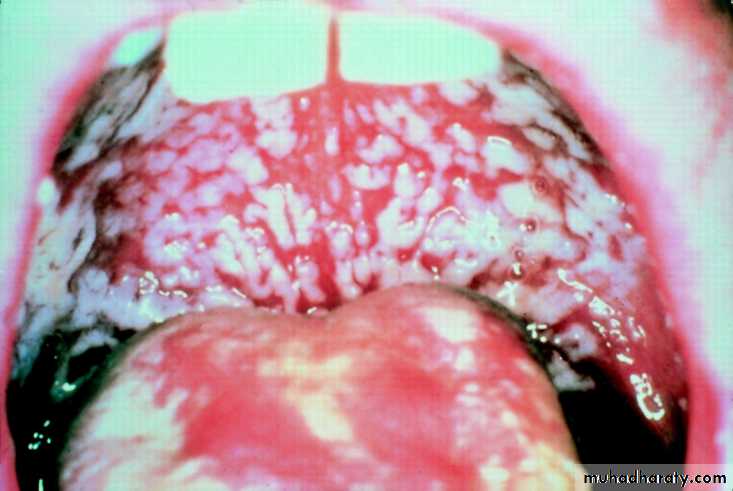

Oral thrush